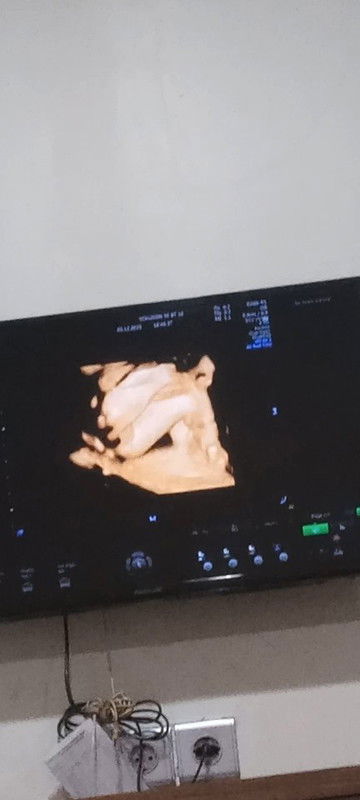

Jenis kelamin

Apa bener moms ini cewek, Soalnya kata obgyn nya waktu itu perempuan ada belahan nya,,tapi aku aga ragu dikit ,menurut moms gmna ya? Aku kurang tau moms,soalnya baru pertama kali hamil,,waktu itu aku usg 4d usia kandungan 25 w 4d #mohonbantujawabbunda #Sharingdong_Bund #bantujawab